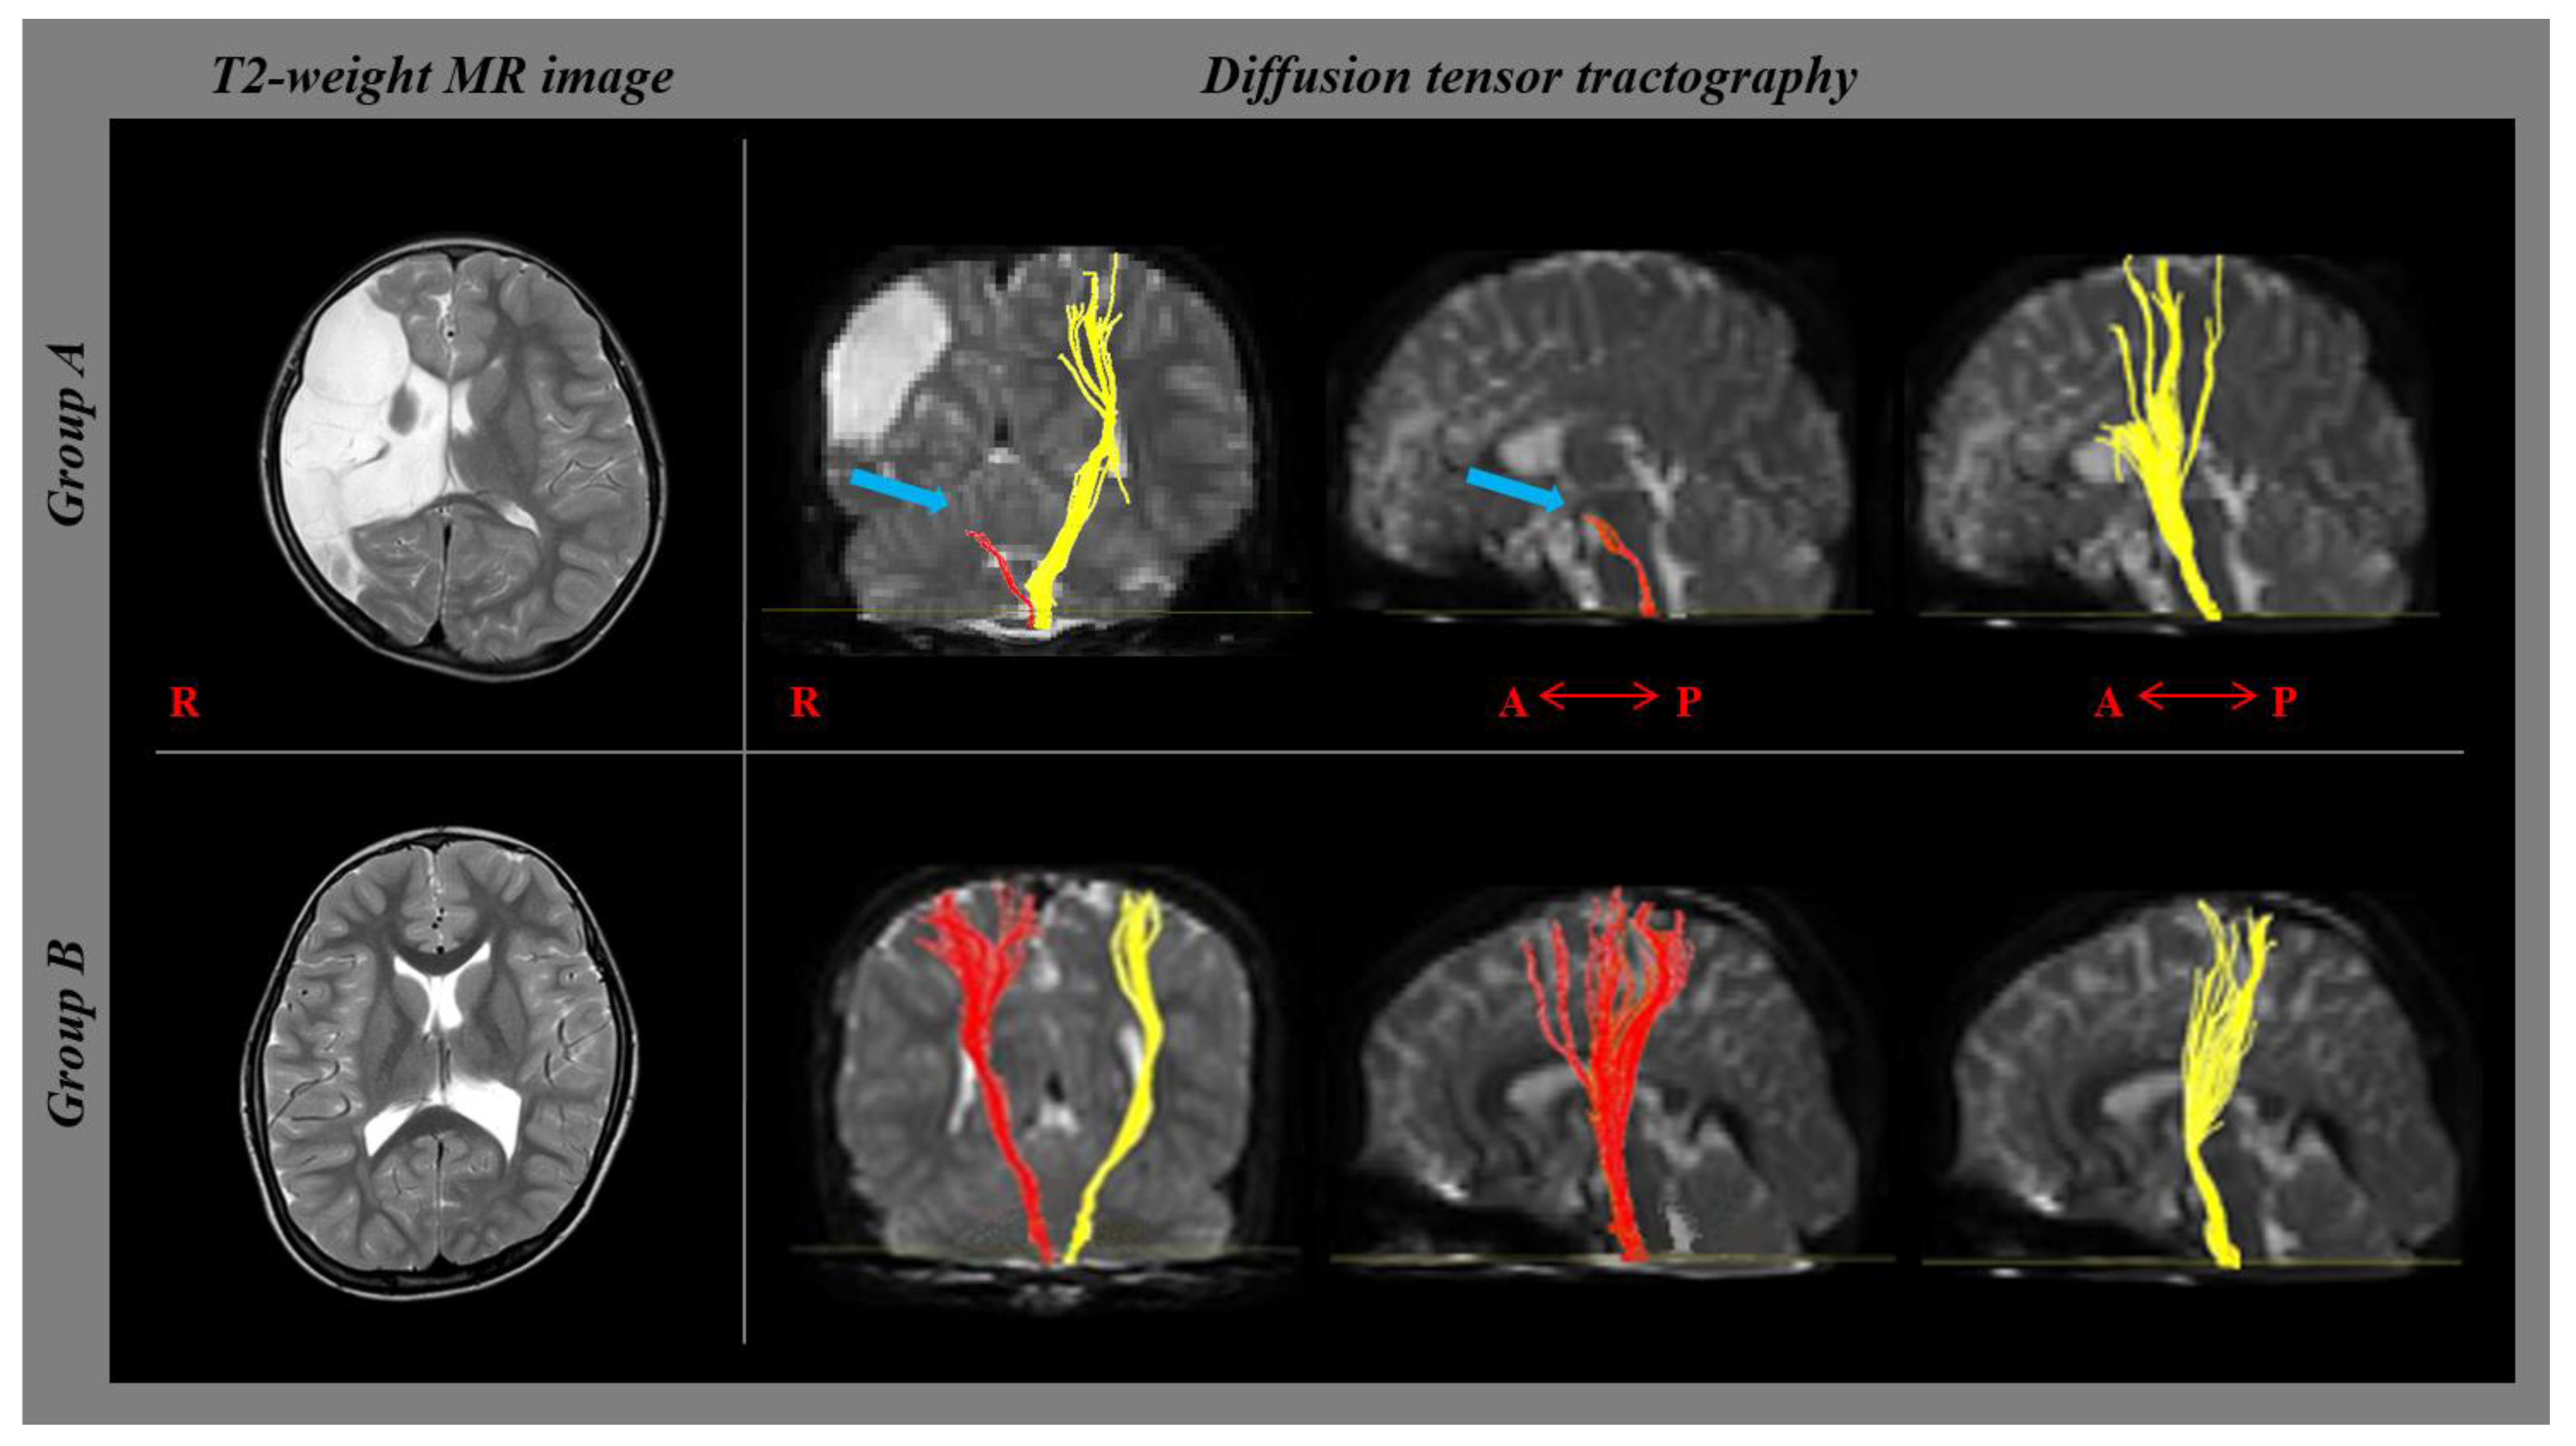

| Degree of CST disruption (1/2/3) | 26/21/- * | -/-/45 * | <0.001 * | ||